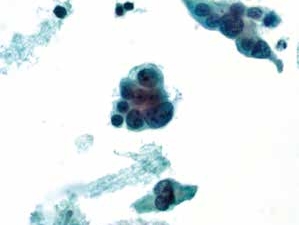

图4-31 高度鳞状上皮内病变(HSIL)(高倍、液基、巴氏染色)

异型增生的细胞密集成团,胞核明显增大,核膜不规则,核质比明显增高。

图4-32 高度鳞状上皮内病变(HSIL)(高倍、液基、巴氏染色)

细胞核异型性明显,染色质粗颗粒状,核膜不规则,胞质浓染,核质比高。此为异型性明显的不成熟化生细胞,判读为HSIL。